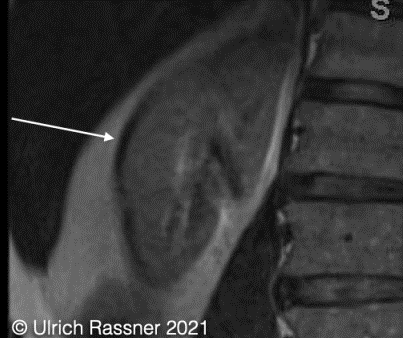

chemical shift artifact, of the first kind

occurs in the frequency encoding direction.

black –> white is the direction of the frequency encoding direction.